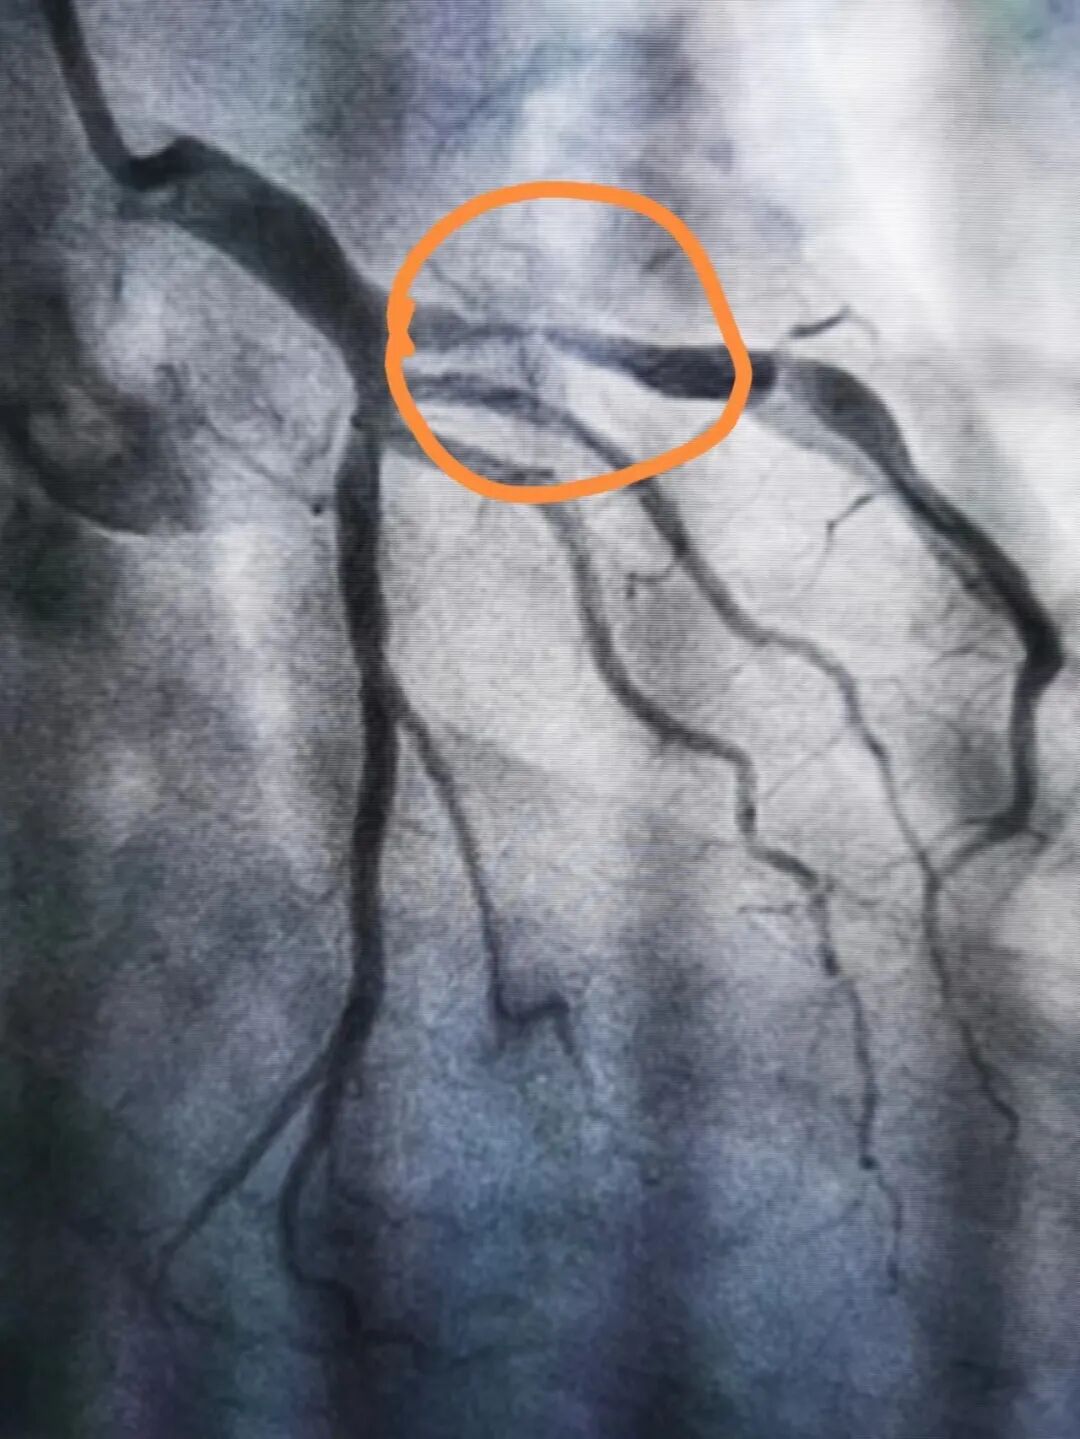

近日,我院心内科主治医师罗明慧接诊了一例持续胸痛2小时的病人,初步怀疑为“急性心梗”。在急诊行冠状动脉造影后,发现患者前降支次全闭塞,只剩下一根头发细的血流,需要立即行冠状动脉球囊扩张和支架植入术解除冠脉梗阻。

冠脉梗阻解除前后对比

我院心内科团队经过不到半小时紧张有序的操作,患者马先生的冠状动脉球囊和支架植入手术最终成功完成,闭塞的血管重新开通后,患者胸痛的症状即刻得到了缓解。